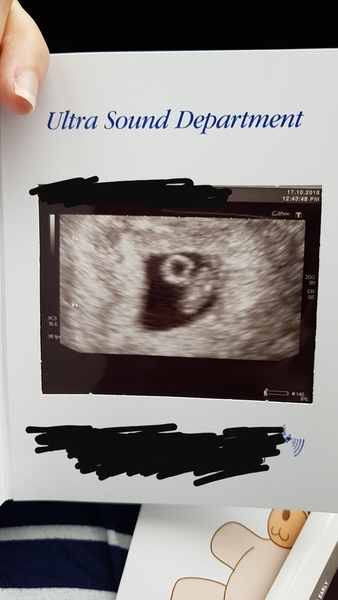

Hiya, early scan went well. One happy healthy little baby, measuring at 6+5 instead of 7+1, but I did think that may be the case. The round white circle is the yolk sac, and the blob next to it is baby. He/she had a good heart beat! All good!

Great news @Stormwhale, congratulations! What a clear scan too! x

Wooohoooo @Stormwhale how exciting!! Lovely to see this!

Great scan pic @Stormwhale pleased the scan went well!

How wonderful @Stormwhale!

@stormwhale lovely scan picture!

Storm lovely scan picture, great news all looking good, congratulations.

Great scan pic Stormy. Glad all is well.

Thanks everyone. I feel really relieved all seems to be ok so far. I should have known really as I feel so sick and boobs have their own gravitational force at the moment. We are going to start telling people on the weekend.